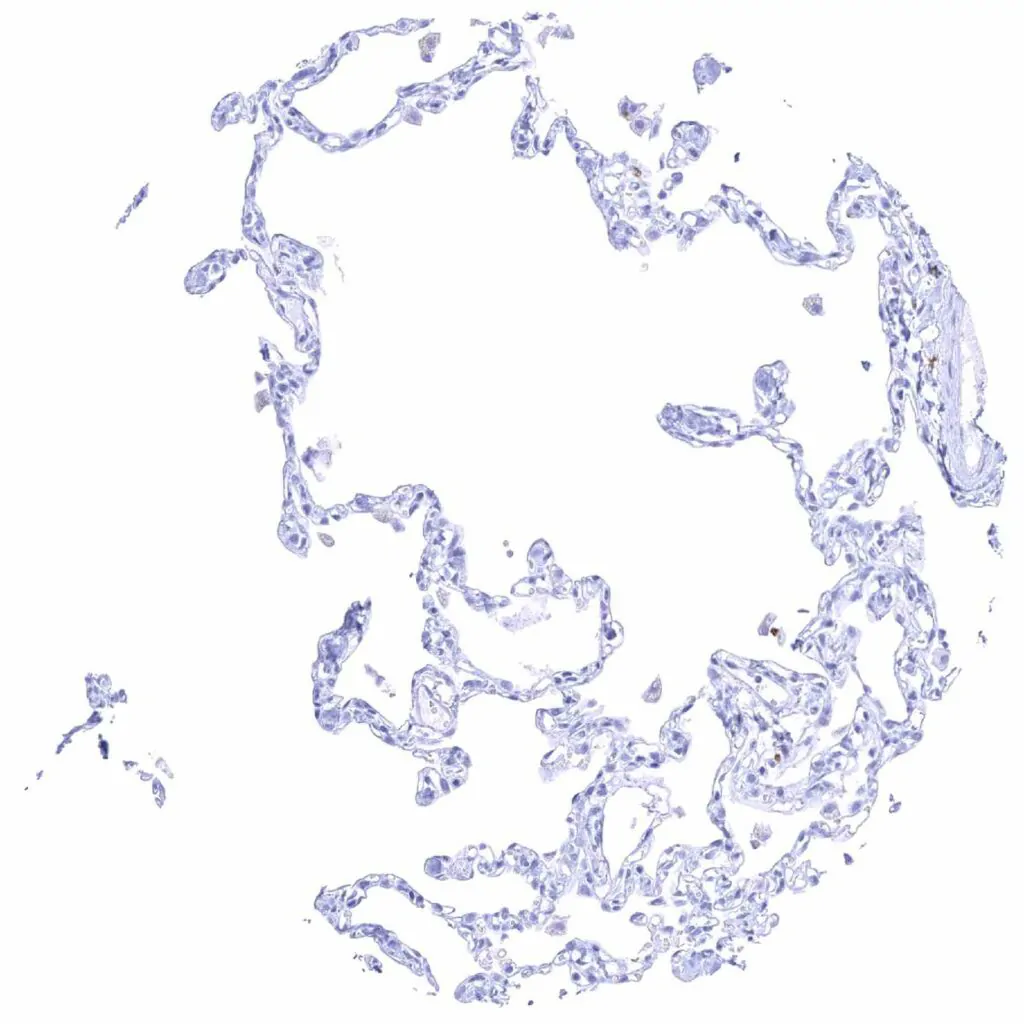

Lung